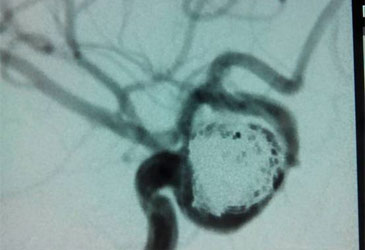

吴英终于能睡个好觉了,断续十二年的头痛顽疾被治愈了,而这让她兜兜转转四处搬家,最终头痛的原因实际上是由颅内动脉瘤引起的。 神经性头...